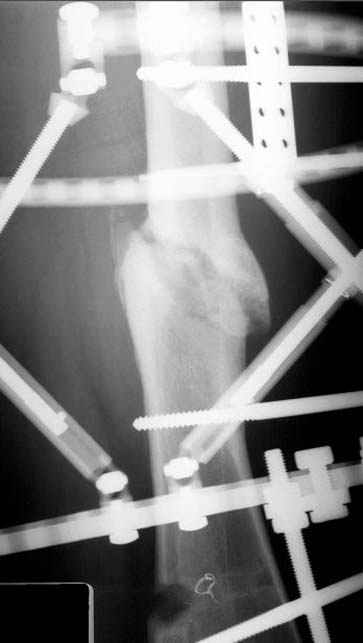

Несколько снимков из моей коллекции, чтобы разьяснить, почему мы до сих пор делаем различные варианты остеотомии.

На рисунке N1 предоперационный план лечения ложного сустава шейки бедра- линия ложного сустава, угол и направление введения импланта, клиновидная остеотомия в градусах и миллиметрах, второй снимок после коррекции, расчет, на сколько удлиняется конечность и размеры импланта;

N3 рисунок окончательный снимок, после операции моя рентгенограмма должен выглядеть примерно как эта картина. На N4 снимке клин перед удалением; N5 послеоперации 3 нед.; N6 окончательная рентгенограмма.

пластическая модель; и коррекция бедра аппаратом Илизарова.